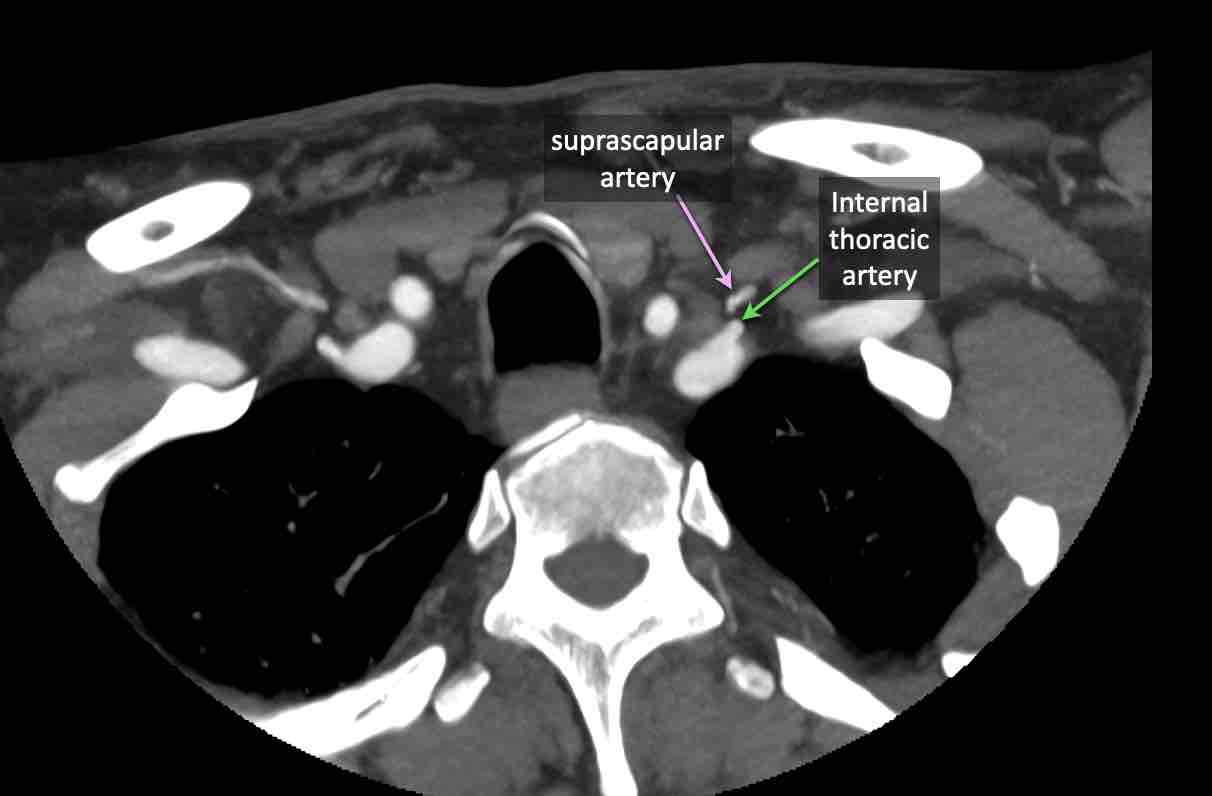

Động mạch cổ ngang

Cuộn qua các hình ảnh để xem giải phẫu của động mạch cổ ngang.